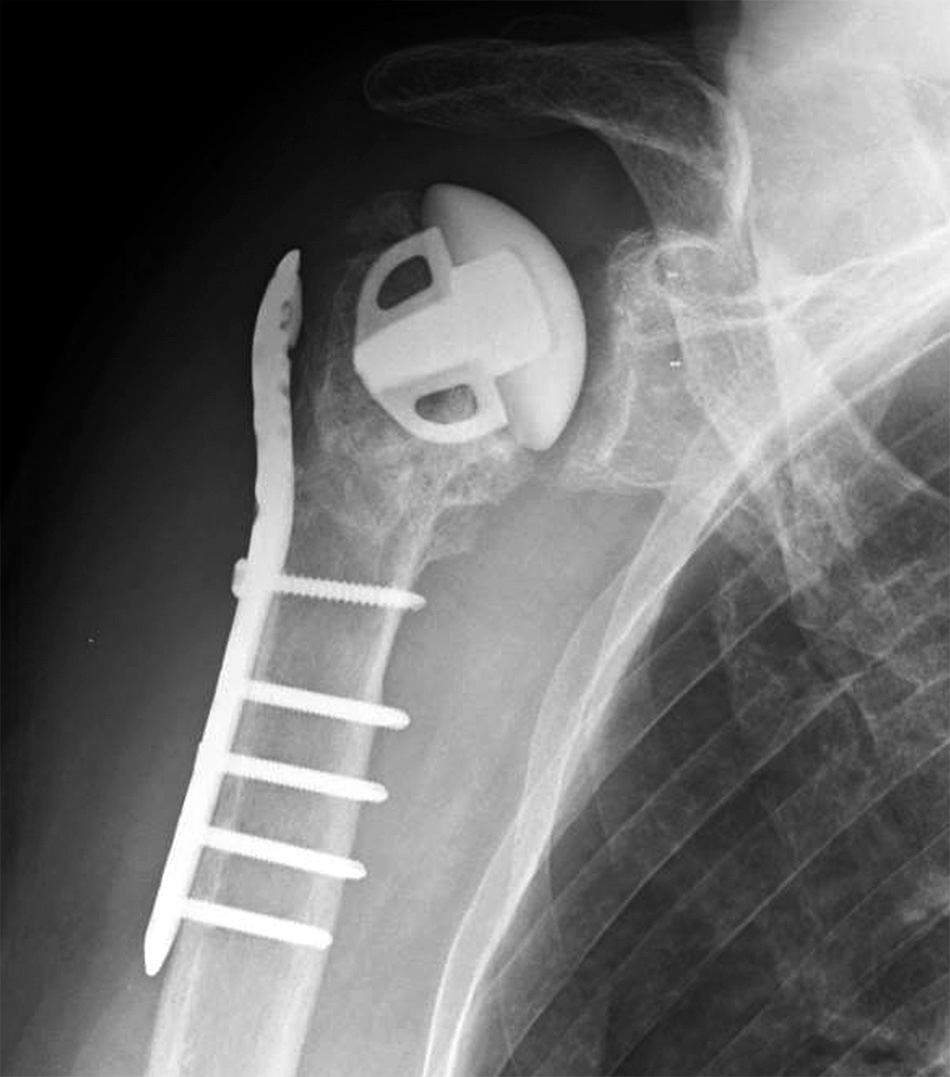

肱骨近端骨折手术后的肱骨头坏死

肱骨头置换还是内固定